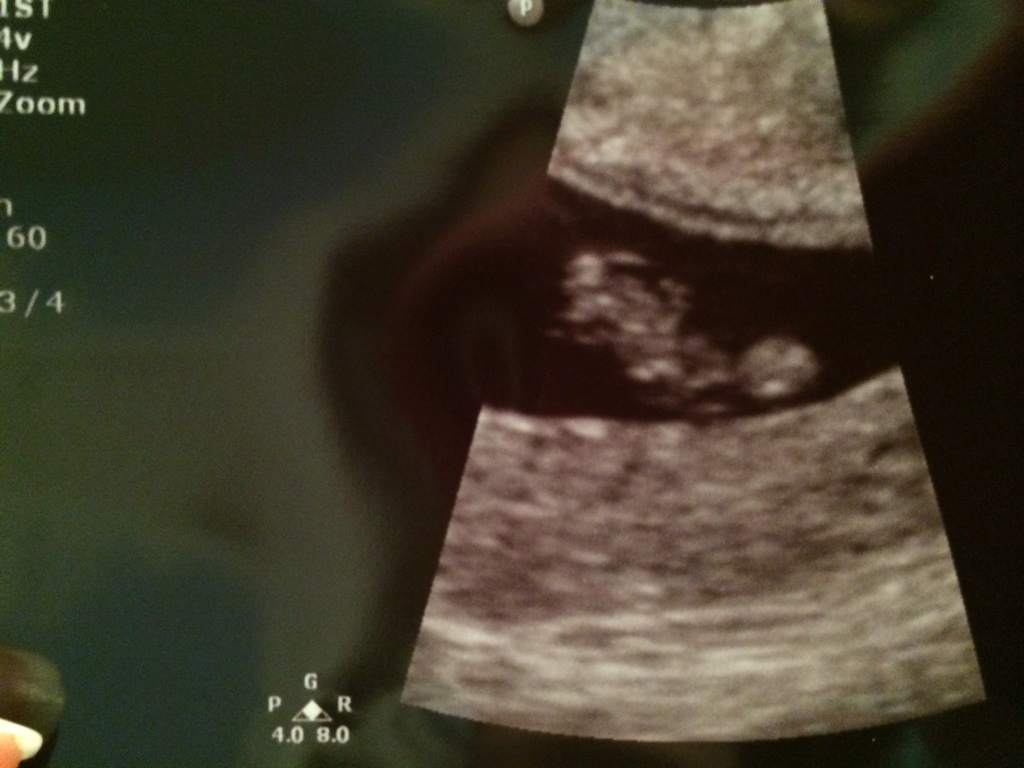

Heard our twins' heartbeats today. It feels so surreal!! Then the doc said uh-oh....there's a third sac! Unbelievable! No heartbeat but it definitely has us on the edge of our seats!